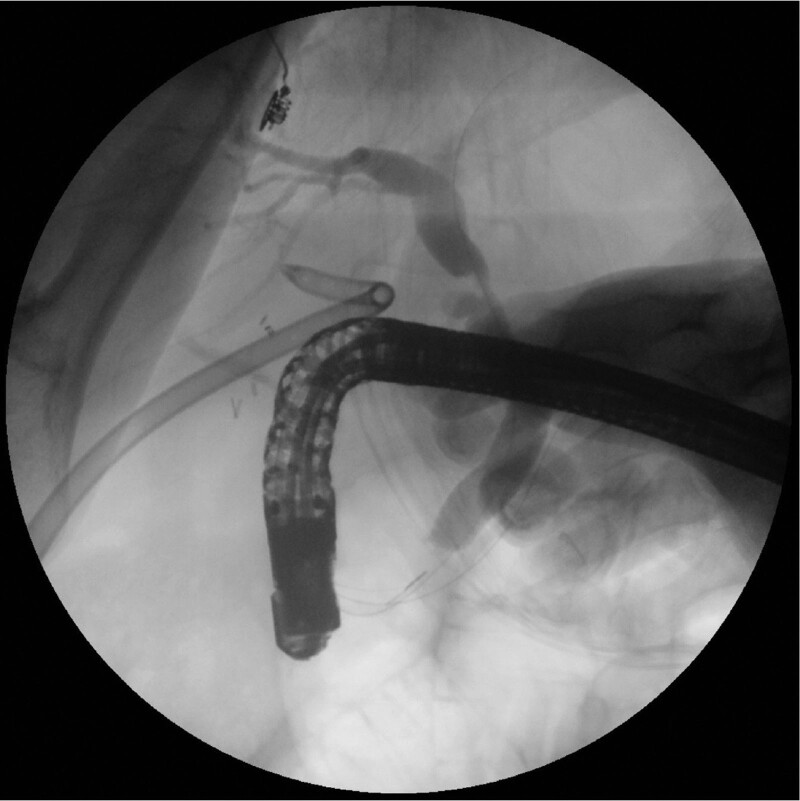

About 4 weeks later, the patient was readmitted for ERBD removal. The balloon dilation had been used to increase the size of the percutaneous gastrostomy track. After sequential dilatation of the gastrostomy track, a fully covered self-expanding esophageal metal stent (Taewoong Medical, Seoul, Korea) was deployed within the gastrostomy tract. After the stent was fully expanded, antegrade ERCP was performed through the percutaneous stent (Fig. 4). Under fluoroscopy, bile leakage was not observed. We removed the ERBD. After the ERCP, a 26-Fr balloon bumper PEG catheter was inserted at the gastrostomy site, which was subsequently removed for 2 weeks for tract maturation. The patient was discharged without any complications on the 15th day. There were no long-term complications noted during the 12-month follow-up. This case study was approved by our ethics committee (Gyeongsang National University Hospital, GNUH 2022-04-008) and was performed in accordance with the ethical standards of the Declaration of Helsinki.

We performed a procedure similar to that reported by Koggel et al,[15] which involves placement of 4 sutures in a diamond-shaped purse string in the gastrotomy site to lift the stomach and prevent gastric contents from spilling into the peritoneal cavity. After termination of LA-ERCP with biliary stent insertion, a 26-Fr balloon bumper PEG catheter was inserted through the 15-mm trocar site for the re-ERCP procedure. Complete closure of bile leakage generally takes 4 to 7 weeks.[16] Therefore, we removed the ERBD stent 4 weeks after the procedure. For passage of the endoscope through the PEG site, sequential dilatation of the PEG site and a fully covered self- expanding esophageal metal stent (Taewoong Medical, Seoul, Korea) were deployed within the PEG tract. After the stent was fully expanded, antegrade ERCP was performed through the percutaneous stent, and the stent was removed successfully.